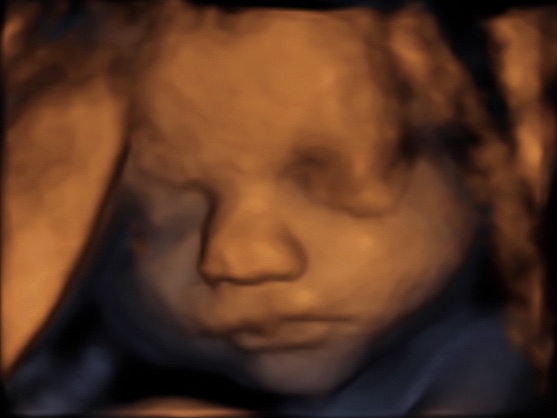

30 weken